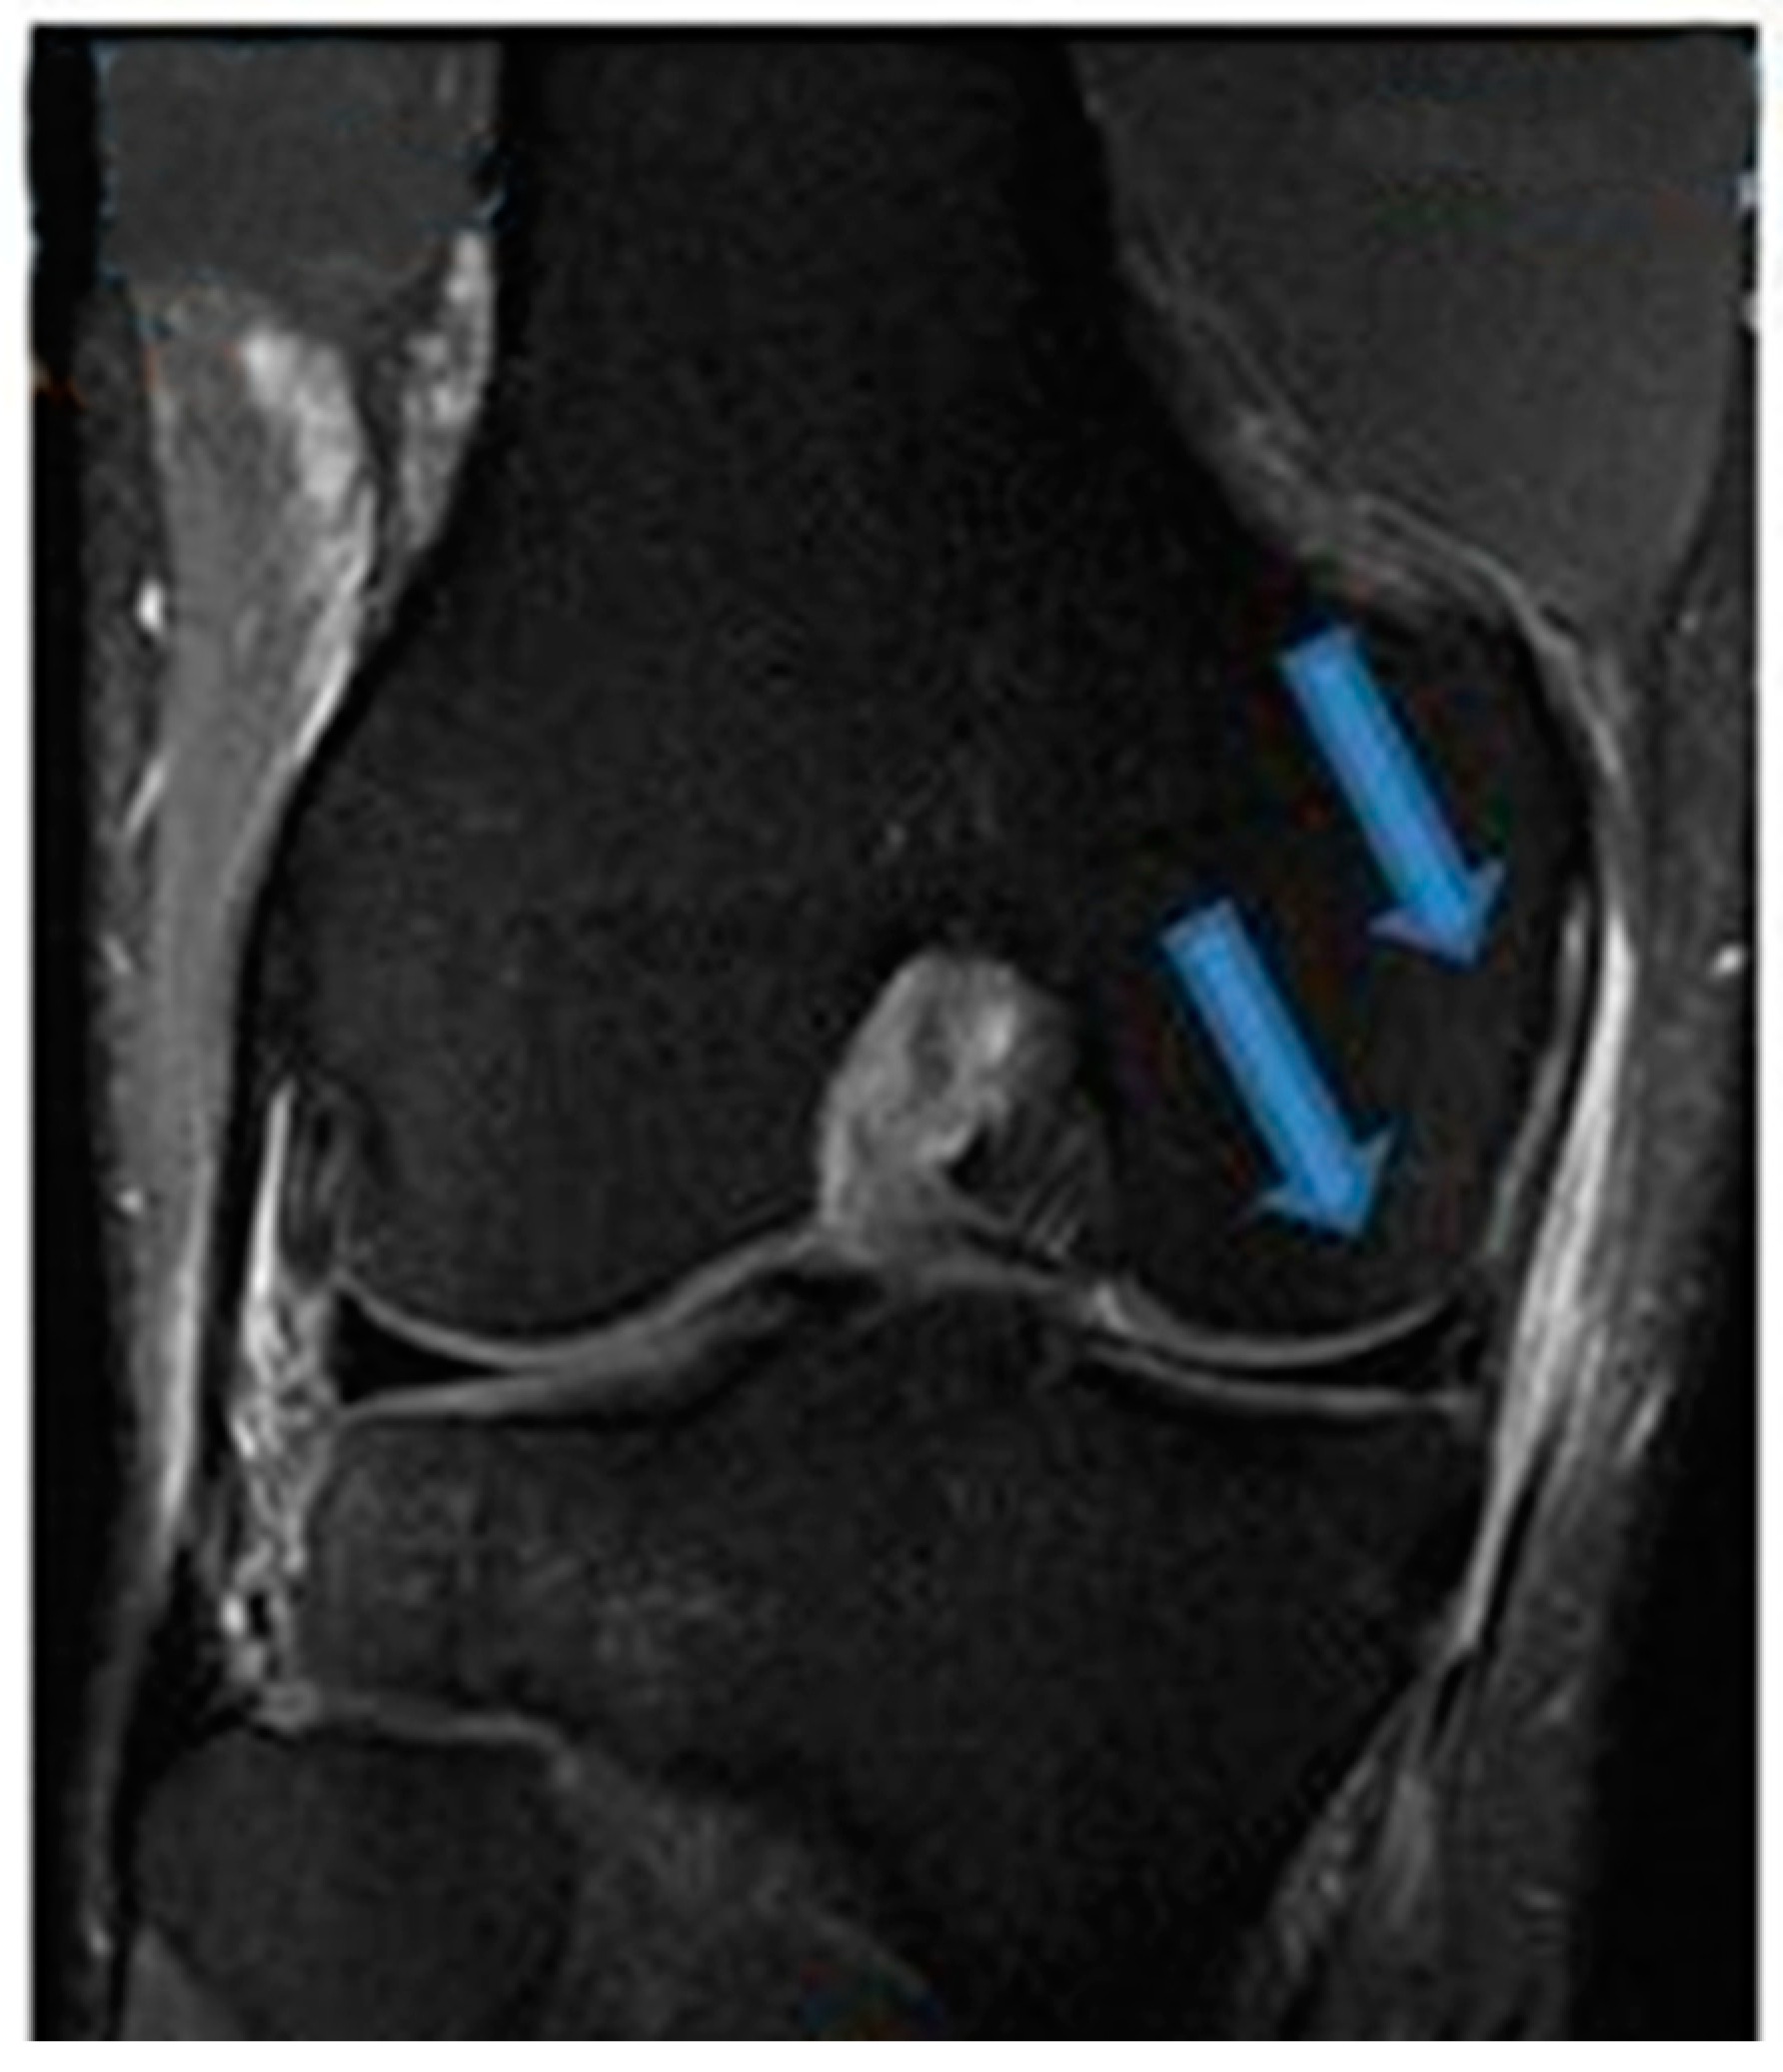

| 14 August 2021 | MRI scans demonstrating signs of complete ACL healing |